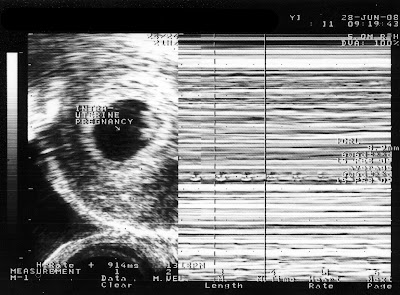

I was of course overjoy. Below are the series of ultrasound scans. The first was done roughly when he was 8 weeks old. He looked just like a kidney bean on the right of the black circle. BTW the black circle is the womb. This scan is basically to confirm he is well settled in the womb and not anywhere else (like the fallopian tube). Then when Prof. Ng measured his heartbeat, hearing the heartbeat of the fetus for the first time, the feeling was indescribable.

The second scan three weeks later showed the growing fetus and the placenta. His heartbeat was 171bpm then. Must be excited about us checking him out.